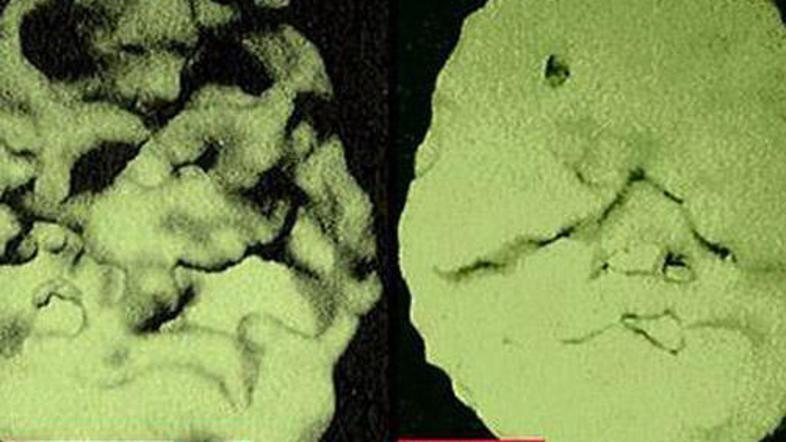

Ameriški nevrolog Daniel G. Amen je predstavil šokantno primerjavo možganov človeka, ki kadi in pije kavo, z zdravimi možgani.

Znano je, da je kajenje in uživanje drog škodljivo za zdravje. Da pa lahko slednje povzroči takšne spremembe, kot jih je predstavil ameriški nevrolog, pa je za marsikaterega šokantno. Kot je razvidno iz fotografije, je mogoče na levih možganih videti velike črne luknje, ki so posledica kajenja, kofeina in uživanja drog.

"To so mrtva, nedejavna področja možganov, v katerih ni več pretoka krvi,"

pojasnjuje nevrolog Daniel G. Amen. Ob tem pravi, da lahko takšno nepopravljivo škodo naredijo tri skodelice kave in dve škatlici cigaret na dan.

"Pacienti, ki kadijo in pijejo kavo, imajo podobno poškodovane možgane kot bolniki z Alzheimerjevo boleznijo," je opozoril omenjeni nevrolog in dodal, da se takšne poškodbe možganov pri ljudeh kažejo na različne načine. Med najpogostejšimi znaki so slaba zbranost, depresija in "luknje" v spominu.